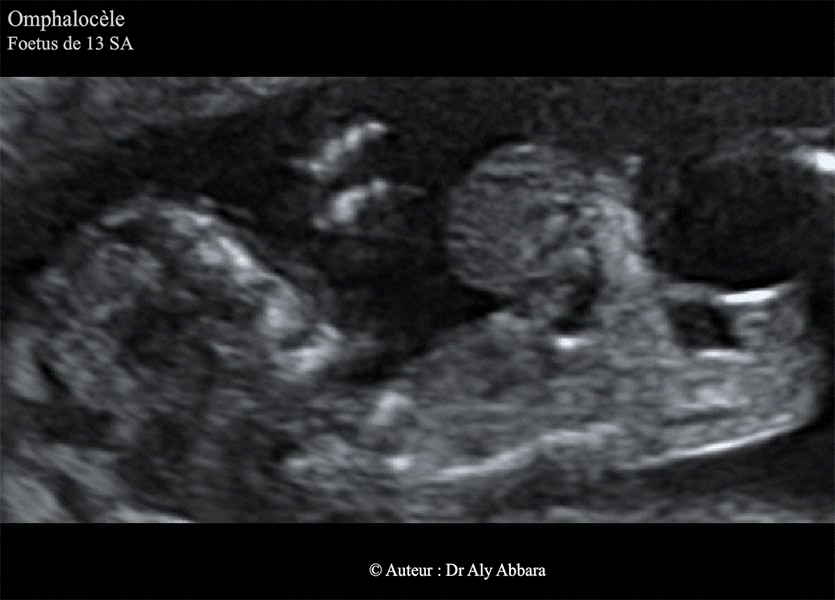

Omphalocèle - Grossesse de 13 SA

• Images échographiques montrant une grossesse de 13 SA caractérisée par la présence d'une volumineuse omphalocèle de 17 x 13 x 19 mm diamètre (2,2 cm3 de volume) contenant une partie des anses grêles et l'estomac.

Les autres anomalies fœtales associées à cette omphalocèle : une hernie diaphragmatique et une anomalie cardiaque (coeur à ventricule unique).